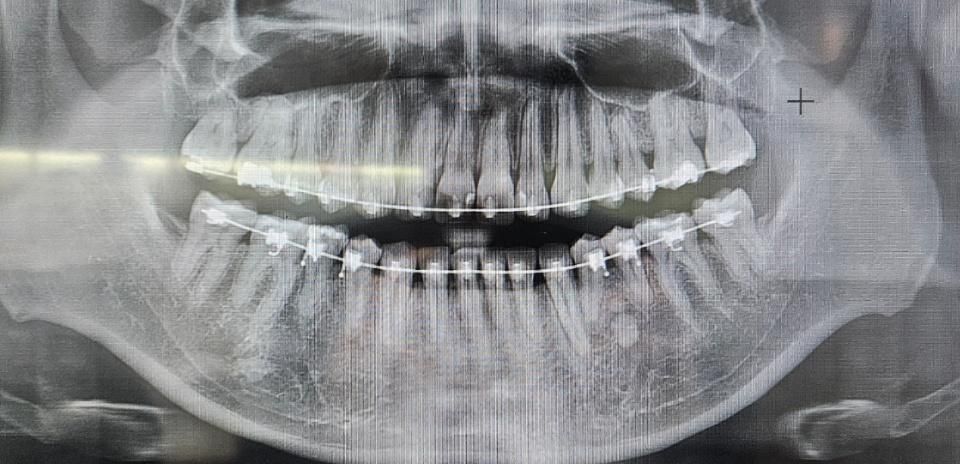

보시면 앞니 1/3 가량이 벌어져있습니다.

잘 보시면 오른쪽 치아가 오른쪽 방향으로 약간 기울어져있습니다.

엑스레이 사진은 좌우 반전된 겁니다. 엑스레이에서도 잘 보시면 살짝 기울어져있구요.

1. 엑스레이랑 사진으로 봤을 때, 정상 범주 안에 드는 것인가요?

2. 앞니 끝 부분을 추가 교정할 수 있나요? (엑스레이 사진 첨부)

엑스레이 상으로는 크게 문제가 잇어 보이진 않습니다. 앞니의 경우에는 레진으로 공간을 메꾸시고 더이상 교정으로는 공간을 메꾸는건 안될꺼 같습니다.

교정으로 해결할 수 있는 문제는 아닌 것 같습니다. 원래 두 앞니의 컨택 포인트가 다소 낮고 #21의 근심 우각이 완만한 둔각((-> 사진상 왼쪽 앞니의 끝부분이 직각이 아니고 완만한 곡선 둔각)이기 때문인데 그게 앞니 사이 공간이 있다, 벌어져 있다고 하진 않습니다. 즉, 정상 embrasure (치간공극) 인 겁니다.